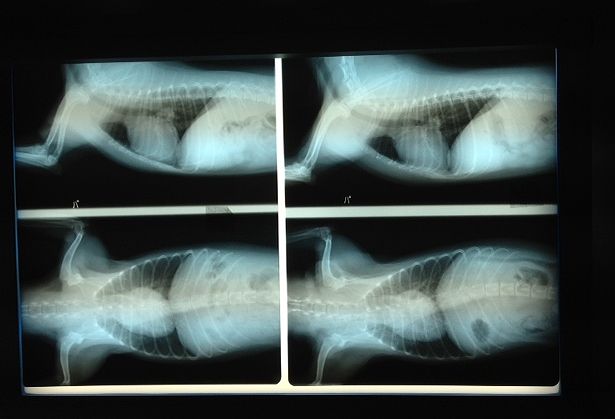

まずは胸部から。

向って右側が昨年の写真、左が今年の写真です。

黒く写っているのは肺で、その真ん中にあるのが心臓だそうです。

心配していた心臓の肥大はほとんどないようでしたが、背骨の尖ってきている部分が去年よりも若干増えたとの事です。